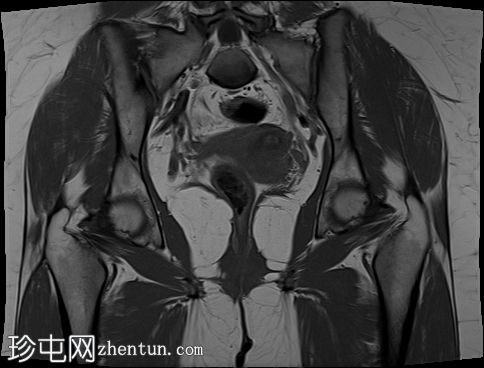

冠状位

斜位T2加权像

子宫外底轮廓清晰,肌层较厚,将子宫内膜腔分隔成两个腔,纤维层较薄,向下延伸至宫颈外口。子宫内膜厚度正常,两个子宫腔交界区清晰,未见明显的实性局灶性病变。

卵巢卵泡形态正常,可见多个小卵泡,主要位于卵巢周边,无优势卵泡。未见实性或囊性肿块。

本病例展示了典型的纵隔子宫影像学表现:增厚的肌层隔膜将子宫内膜腔分隔成两个腔,并有一层薄的纤维隔膜延伸至子宫颈外口水平,符合完全纵隔子宫的特征。

在MRI图像上,纵隔子宫通常大小正常,但每个子宫腔的形态均小于正常子宫腔。

隔膜可能由纤维组织(T2信号低)、肌层组织(中等信号)或两者共同构成,如本病例所示。